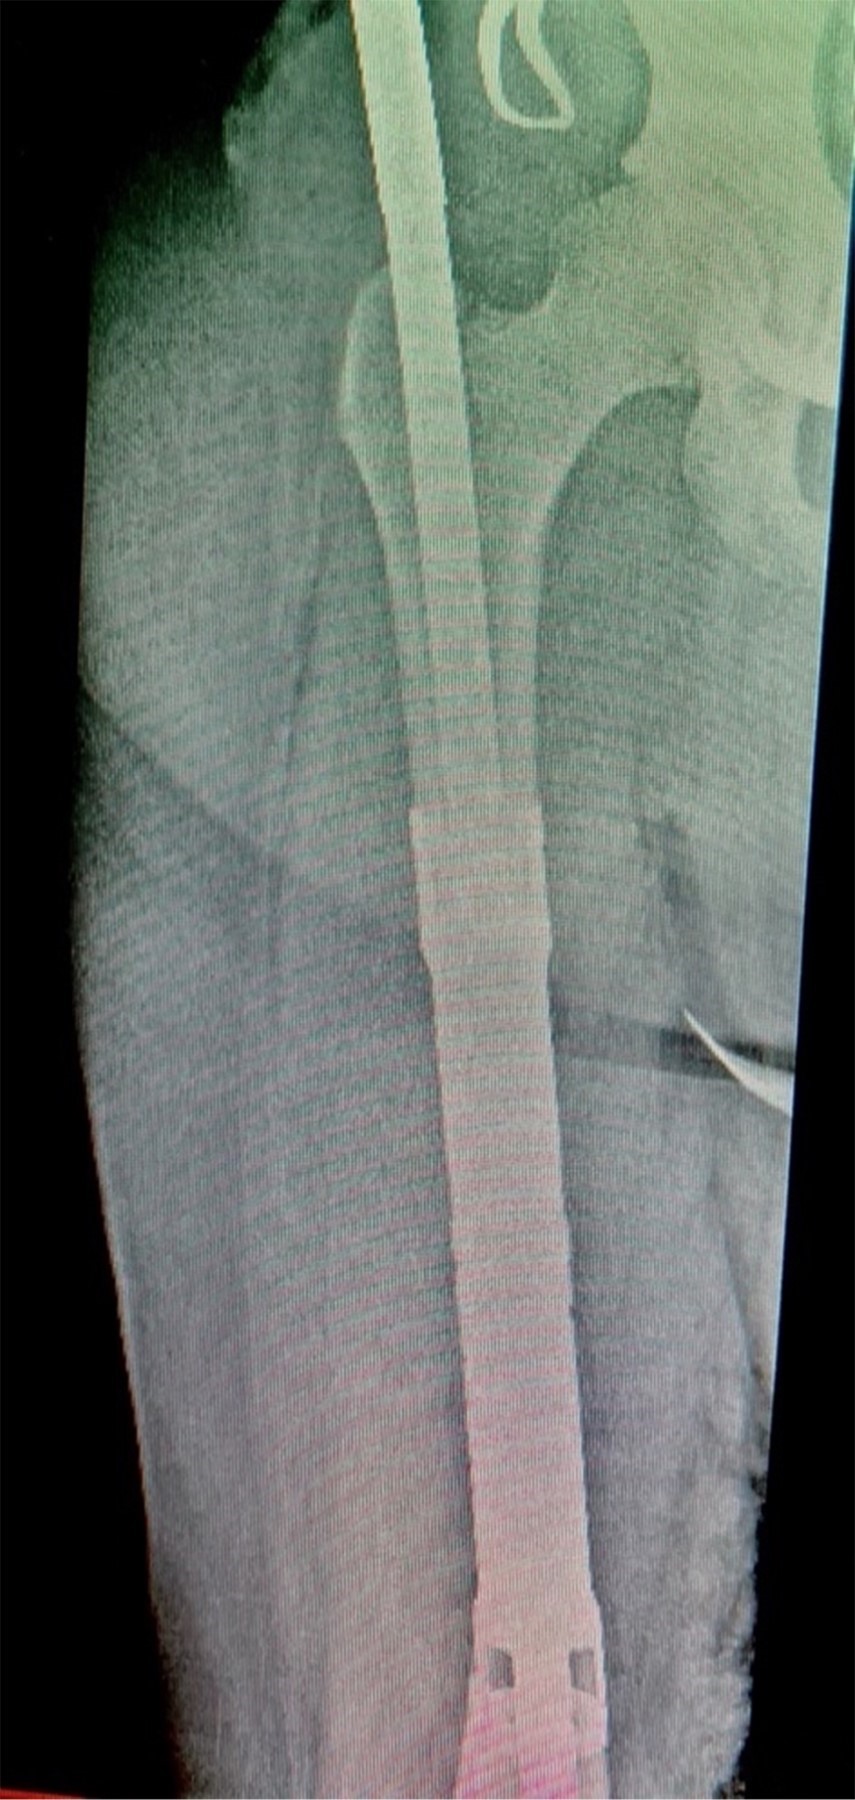

Con la paciente bajo anestesia general y en decúbito supino, se realiza asepsia, antisepsia y colocación de campos quirúrgicos estériles. Se opta por un abordaje anteromedial de fémur, mediante incisión longitudinal de aproximadamente 25 cm, disecando por planos hasta encontrar intervalo entre músculos recto femoral y vasto medial; después se encuentra el vasto intermedio, el cual se diseca hasta encontrar diáfisis femoral. Se observa tumoración en tercio medio de diáfisis femoral de aproximadamente 13 cm de longitud por 3 cm de ancho, el cual se reseca con bordes amplios, realizando osteotomía a 16 cm proximales de superficie articular de la rodilla (Figura 3); se envía muestra medular transquirúrgica, recibiendo confirmación de presencia de bordes libres por el Servicio de Patología. Se realiza segunda osteotomía a 16 cm distales del trocánter mayor, se envía segunda muestra de médula ósea, recibiendo reporte negativo para células malignas. Se realiza rimado de fémur proximal y distal con rimas diámetros 9, 10 y 10.5 hasta atravesar fosa digital proximalmente; se coloca asentador para hueso, regularizando el límite de la osteotomía. Se introduce clavo endomedular hasta limite distal establecido (Figuras 4 y 5) y se coloca prótesis diafisaria (Figura 6) con asentadores y coronas en extremos diafisarios, respectivamente. Se procede a colocar pernos de bloqueo, verificándose longitud de extremidad (Figura 7) comparando con la contralateral. Se repara intervalo entre recto femoral y vasto medial y se procede a cierre por planos.

Figura 5

Figura 6